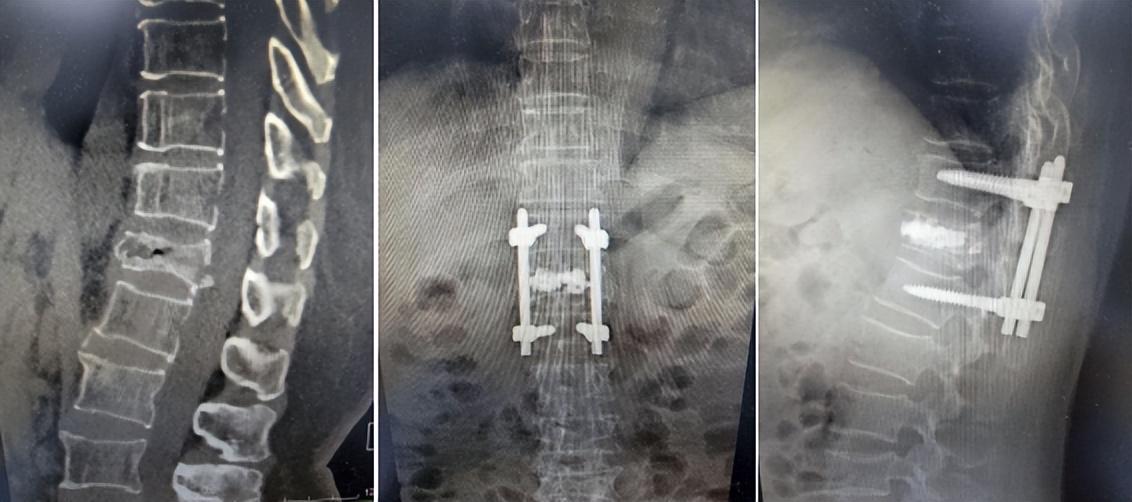

近期,胸椎爆裂性骨折患者龚阿姨在苏州高新区人民医院骨科接受杂交手术(即椎弓根钉棒技术+椎体后凸成形术)后,终于能够开始正常行走,她激动地对骨科主任刘勇博士说:“我现在终于能够站起来走路了,这种感觉太好啦!”

60多岁的龚阿姨来自本省外市,因不慎摔倒,造成胸12椎体爆裂骨折,椎体压缩严重(超过了椎体高度的二分之一),当地医院计划给予实施椎体成形术,但因考虑其骨折椎体碎裂严重,手术“骨水泥”渗漏风险较大,而且患者椎体压缩超过椎体高度的二分之一,单纯椎体后凸成形手术恐难以恢复高度,造成患者脊柱后凸畸形,故当地医院未能按计划手术。为难之际,龚阿姨通过家人了解到苏州高新区人民医院脊柱微创调节中心成功调节了许多此类骨折病人,于是,其家人满怀希望地带着她前来该院就诊。

该院骨科脊柱疾病微创调节中心主任刘勇博士仔细看了患者资料后,认为可以采用“椎弓根钉棒技术结合椎体后凸成形术”这种杂交手术进行调节。经过前期精心规划、细致准备,手术如期进行。术中,刘勇主任团队先采用椎弓根钉棒进行固定,并复位压缩的胸12椎体;然后,分别于骨折压缩椎体两侧椎弓根注入骨水泥,填充爆裂骨折的骨缺损处,大限度地恢复了椎体的高度,而且通过骨水泥获得了脊柱的稳定性。手术很成功。术后一周,龚阿姨就在佩戴保护支具下开始下地行走了,她的脸上终于露出了久违的笑容。